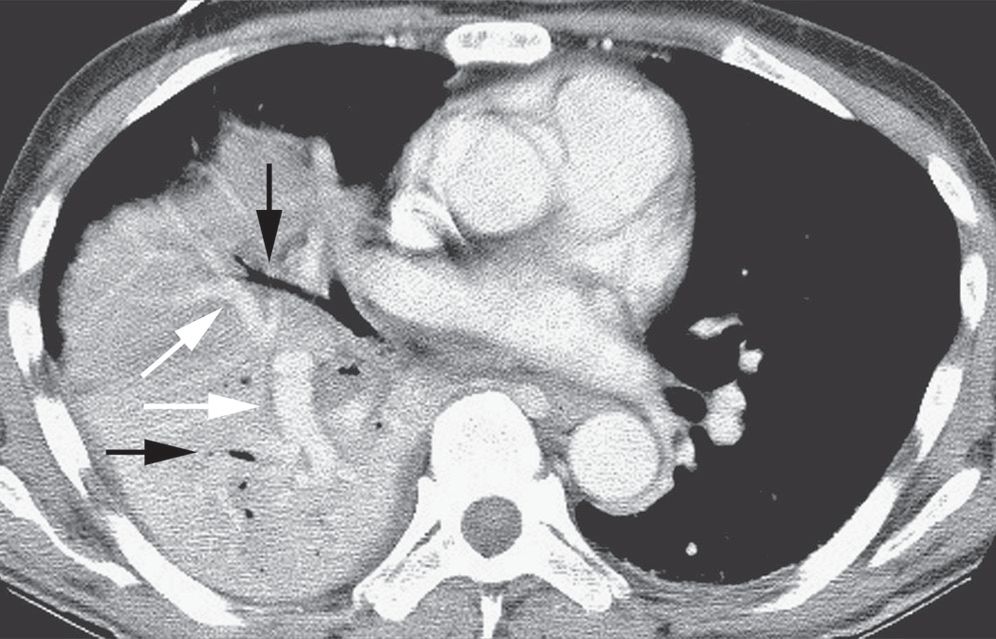

图2-1 实变:均匀致密影,纹理遮盖,空气 支气管征和CT 血管造影征

A.肺水肿所致的右肺实变。可见双侧实变肺内空气支气管征,肺血管模糊;B. 右肺中下叶肺炎患者增强CT 显示病变区均匀实变,肺体积保持不变,空气支气管征( 黑色箭头) 和致密血管影( 白色箭头),其密度高于邻近实变肺组织( 即“CT血管造影”征)

CT血管造影征

肺实变患者CT 的特有征象是“CT 血管造影征”。这是指静脉内灌注对比剂后,在实变肺组织内正常走行的血管影增强呈高密度,在实变影的衬托下显影( 图2-1B,图2-6)。肺部肿块中也可见高密度的血管影,但血管经常表现为压缩和扭曲的形态。

图2-6 实变:CT 血管造影征

肺炎患者增强CT 显示局灶性实变,与实变肺组织相比, 不透明的动脉( 箭头所示) 密度增大,实变边界在斜裂后部分出现